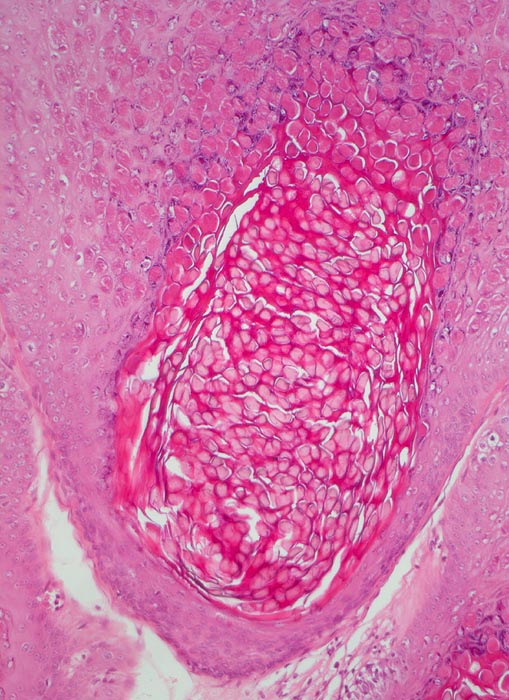

PathoPic – image database / PathoPic ID 5107 - Molluscum contagiosum

Molluscum contagiosum

Kugelige eosinophile intrazytoplasmatische Einschlüsse sind vor allem in Zellen des $o{qy8042178Stratum granulosum} Stratum granulosum und des Stratum corneum erkennbar.

Perianal kleine linear angeordnete Hautpapeln.